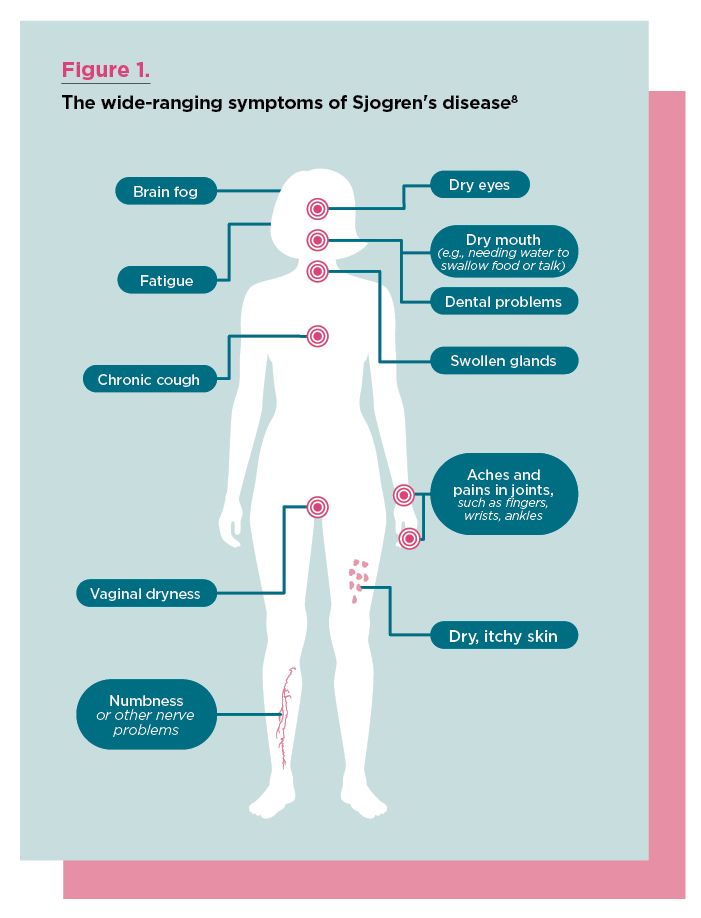

Once thought to be rare, Sjogren’s disease is now known to be the second most common autoimmune rheumatic disease behind rheumatoid arthritis (RA)—and up to half of patients with Sjogren’s present with another autoimmune disease such as RA or lupus.1,2 What’s more, the heterogeneous and often nonspecific manifestations are easily mistaken for other conditions. Such challenges help explain why it can take an average of three years for patients to receive a diagnosis.2 This lag time can pave the way for Sjogren’s progression, greatly impacting a patient’s quality of life (QoL) and increasing vulnerability to organ involvement.

Tuning into symptoms

“We need a lot more education about Sjogren’s disease,” says Dr. Kapoor. The presentation of the disease is not always obvious, and symptoms are nonspecific. For example:

- The most common symptoms include dryness (eyes, mouth, skin, airway and vagina), fatigue and musculoskeletal pain.

- Systemic manifestations may lead to joint swelling, shortness of breath and cough (interstitial lung disease; ILD), rash (skin vasculitis), paresthesias and/or weakness (peripheral neuropathy), dizziness, nausea, dyspepsia, lower urinary tract symptoms, abnormal sweating (autonomic dysfunction) and many others.

Overall, there is a misconception that Sjogren’s is a “dryness disease.” While dryness is a hallmark symptom, some patients experience minimal issues in this area, says Dr. Kapoor. “Clinicians may see a group of patients where dryness is the main symptom. However, up to 40% of patients have systemic manifestations.”